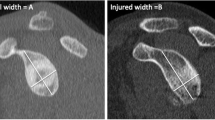

Flatow method

According to the first description by Flatow et al., with this measurement method the relevance of the HSL is assessed based on the compromised humeral cartilage surface in relation to the total diameter of the humeral head using a transaxial view. In this method, the diameter of the humeral head is first determined using a line parallel to the articular surface of the glenoid, without taking the HSL into account. Then, the actual diameter of the humeral head is measured using a line parallel to the first diameter, now considering the bone loss from the HSL (Fig. 4). Finally, the quotient the two diameters is calculated. Lesions with a quotient smaller than 20% are defined as not clinically relevant [17].

The measurement technique according to Flatow et al. The diameter of the humeral head is first measured without the HSL using a line parallel to the articular surface of the glenoid. Then, the diameter of the humerus with the HSL is then determined using a line parallel to the articular surface of the glenoid. Finally, the quotient of both diameters is calculated

Glenoid track

The glenoid track method was performed as recommended by Di Giacomo et al. First, the diameter (D) of the lower glenoid and the extent of glenoid bone loss (GBL) were measured using the best-fit-circle method. Second, the glenoid track was extrapolated using the following formula: GT = (0.83 * D)-GBL. Finally, the Hill–Sachs interval (HSI) was defined as the sum of the width of the HSL and the extent of intact bone between the rotator cuff insertion and the lateral rim of the HSL. The HSL was defined as off-track if the HSI was greater than the glenoid track (HSI > GT); otherwise, it was defined as on-track [13].